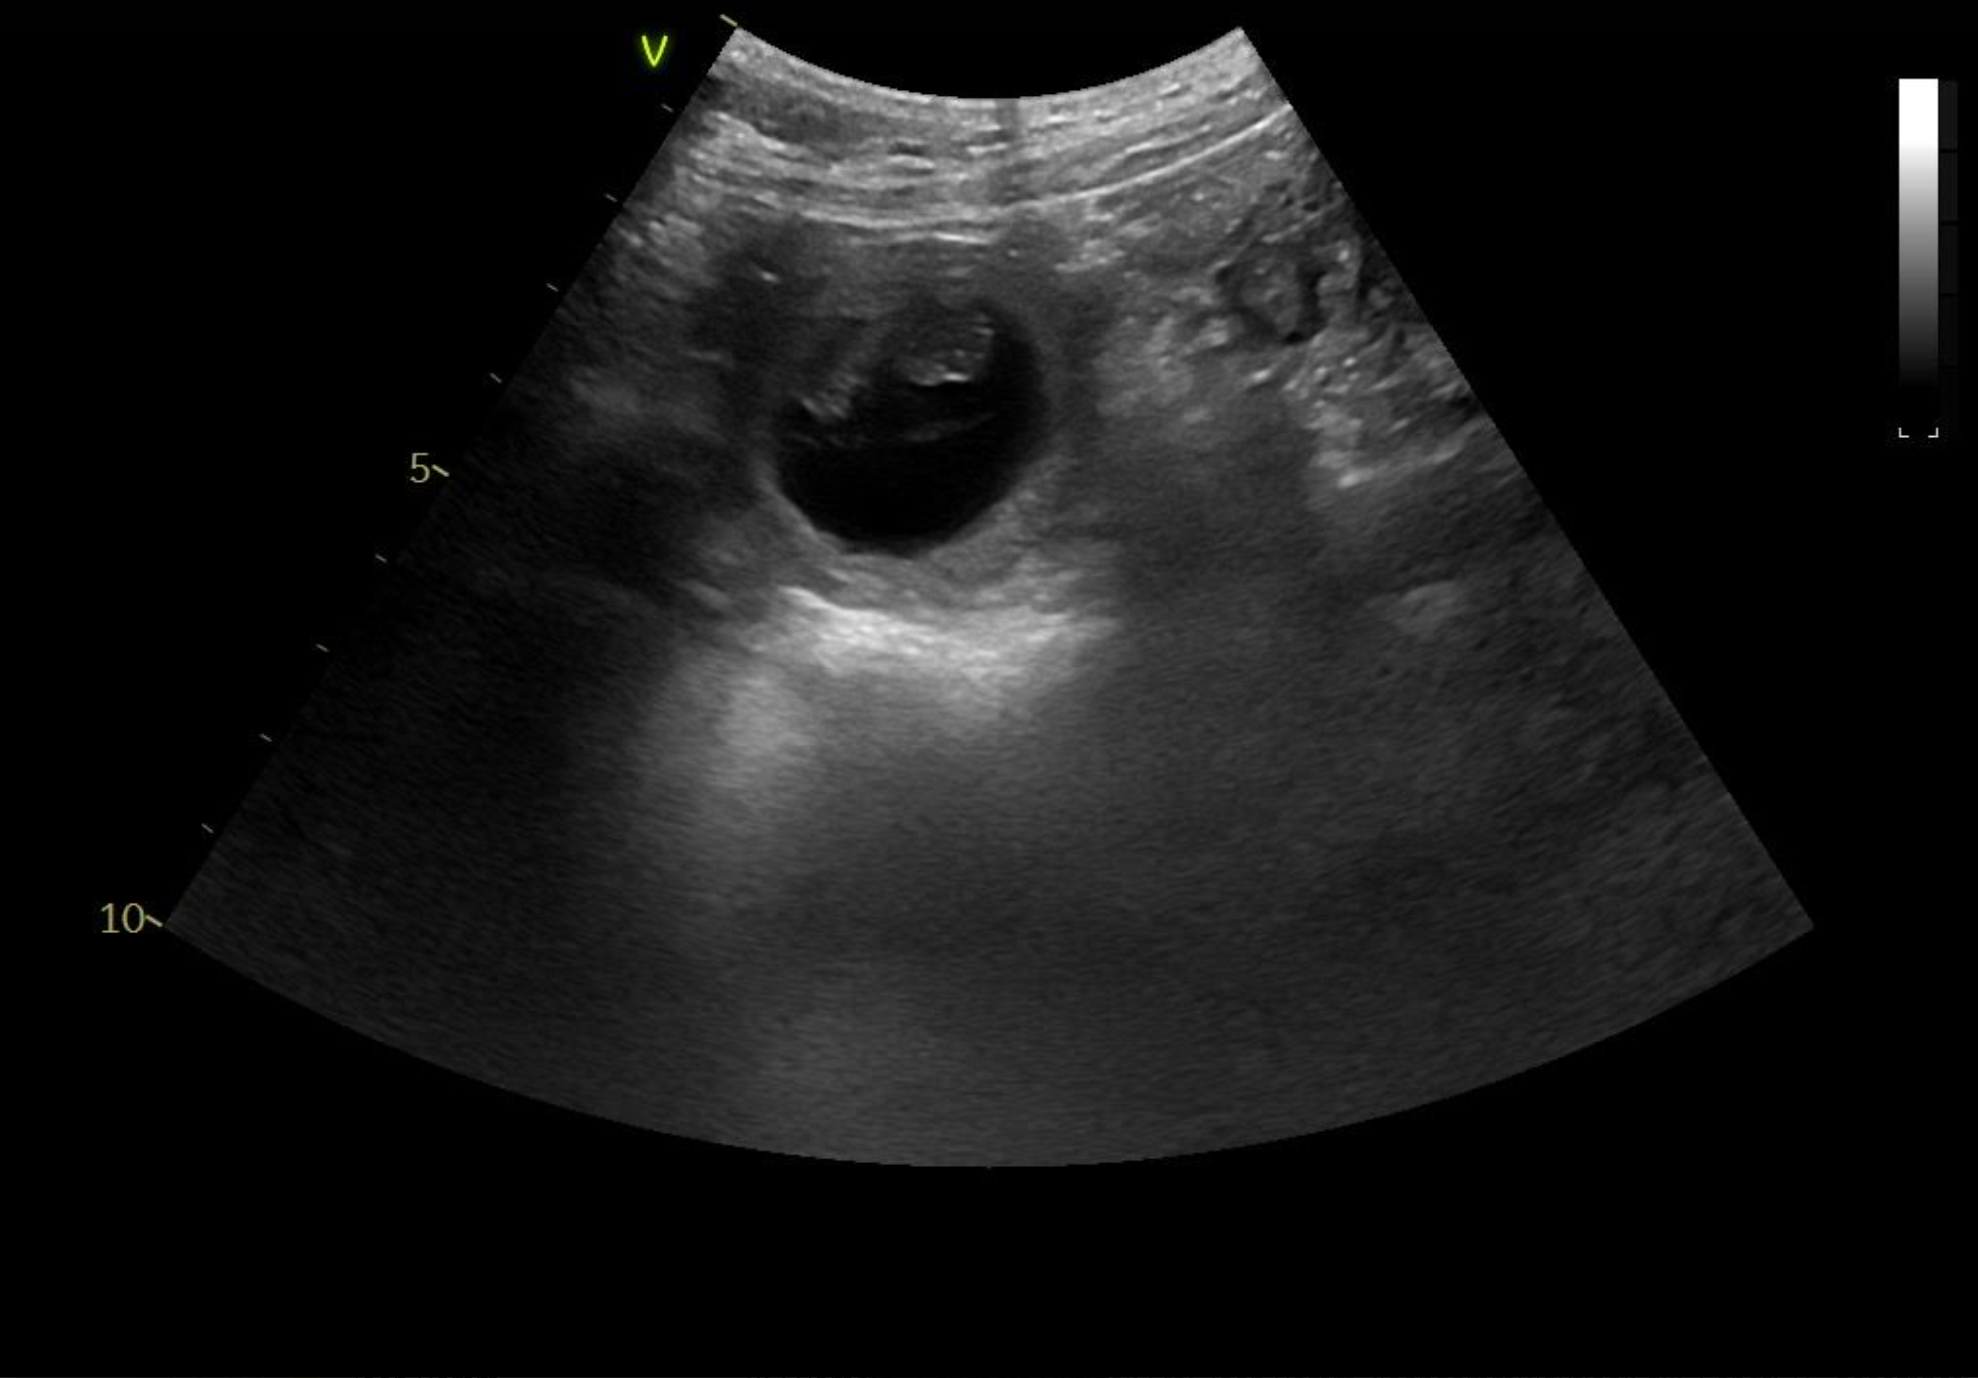

Tessa er scannet igen. Hvalpene er alle i live og har det godt. Deres hoveder er målt til 2 cm.

23.03.2021

Tessa er scannet drægtig. Hvalpene er sunde og er målt til 1,5 cm.